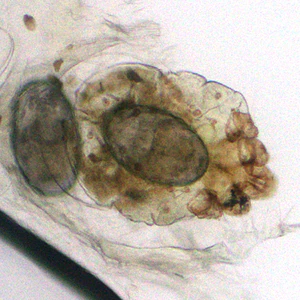

A patient presented to a local hospital with encrusted lesions on his arms and legs. A skin scraping was made and examined unstained at 40x magnification. Figures A and B show what was observed by the attending microbiologist. The images were sent to the DPDx Team for diagnostic assistance. What is your diagnosis? Based on what criteria?

Figure B